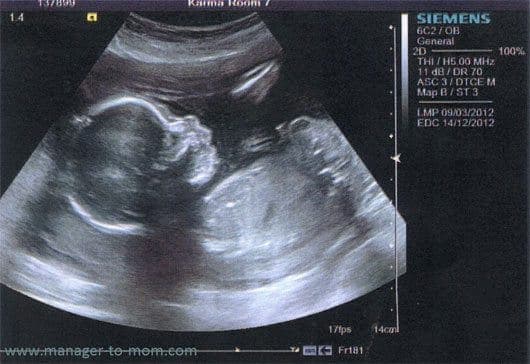

Giai đoạn mang thai là khoảng thời gian tuyệt vời mà chỉ có người phụ nữ mới hiểu và cảm nhận được. Trong những thời gian mang thai này, dựa vào các chỉ số thai nhi theo tuần khi siêu âm mà bác sĩ sẽ đánh gia được sức khỏe của con. Để giúp mẹ có thêm những kiến thức hữu ích, sau đây chúng tôi sẽ chia sẻ chi tiết bảng chỉ số thai nhi theo tuần tuổi đơn giản cho các mẹ, mời các bạn cùng theo dõi nhé!

Chỉ số thai nhi là số liệu và các ký hiệu trên bảng kết quả siêu âm thai kỳ, cho thấy được về cân nặng, nhịp tim, chiều dài xương đùi, chu vi đầu, chiều dài đầu mông, chỉ số nước ối… cho bạn một cái nhìn toàn diện về sự phát triển của thai nhi.

Những ký hiệu phổ biến trong siêu âm thai mà bác sĩ sẽ thường thực hiện, mẹ bầu cần nắm vững đó là:

GA: Tuổi thai tính từ ngày đầu của chu kỳ kinh cuối

GSD: Đường kính túi thai

BPD: Đường kính lưỡng đỉnh, là đường kính lớn ở mặt cắt vòng đầu bé.

FL: Chiều dài xương đùi.

EFW: Cân nặng thai nhi.

CRL: Chiều dài từ đầu mông.

HC: Chu vi đầu.

AC: Chu vi vòng bụng.

Dưới đây là bảng chi tiết các chỉ số thai nhi theo tuần để mẹ tiện theo dõi hành trình phát triển của bé cưng trong bụng.